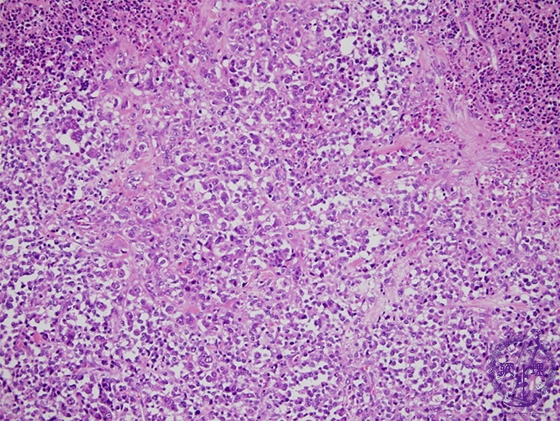

- (6)Rhabdomyosarcoma

Microscopic findings (H.E. low power view): An irregularly-arranged proliferation of round to spindle-shaped small undifferentiated tumor cells admixed with tape- or racket-like or round tumor cells containing abundant eosinophilic cytoplasms. Cytoplasmic cross striations are occasionally identified. Massive intratumoral necrosis frequently detected.